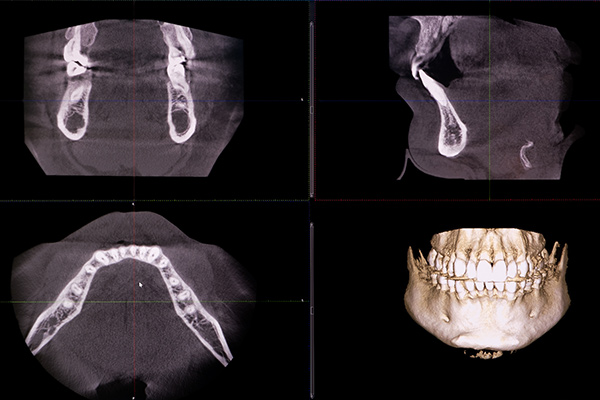

従来の平面的なレントゲンとは異なり、お口の中を3次元的な立体画像で撮影できる装置です。歯の根の形や骨の厚み、目視できない神経や血管の走行までを高精度で把握できます。インプラント治療や高度な歯周病治療において、安全で確実な診断を行うために欠かせない設備です。